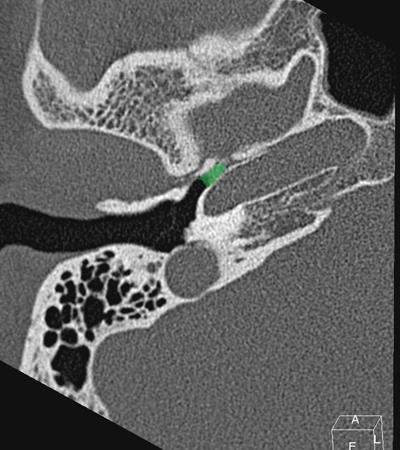

Horizontal petrous carotid Jugula bulb Sigmoid sinus Anterious wall of bony EAC (tympanic bone) Eustachian tube Tympanic membrane Facial nerve (f3), mastoid segment